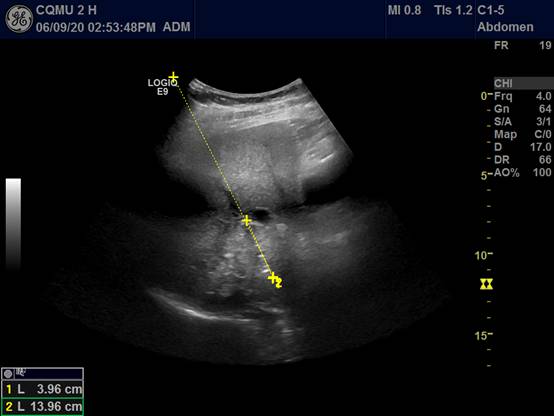

4.消融后再次超声检查,明确治疗效果: